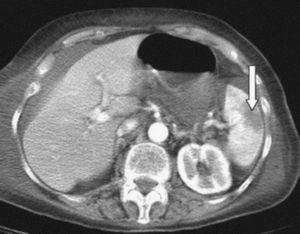

Ante la presencia de un cuadro de dolor abdominal con signos de inestabilidad hemodinámica se realizó ecografía abdominal urgente, en la que se observó abundante líquido libre peritoneal (fig. 1); posteriormente, y tras estabilizar a la paciente, se realizó TAC abdominal urgente en la que se observó línea de rotura esplénica intraparenquimatosa (fig. 2).

Figura 1. Ecografía abdominal: líquido libre periesplénico.

La ecografía abdominal es muy sensible para detectar líquido libre intraperitoneal y es la primera prueba a realizar en pacientes con sospecha de rotura esplénica e inestabilidad hemodinámica6.